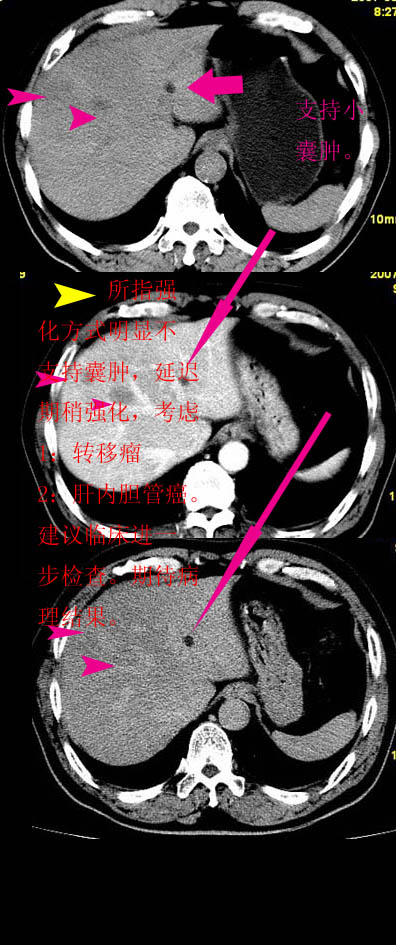

以下是引用拾荒者在2007-8-28 19:41:00的发言:[br]谢谢!肝内多发低密度灶,增强轻度强化,无明显“牛眼征”,不典型肝转移瘤。

以下是引用jane努力在2007-8-9 16:19:00的发言:[br]1 脂肪肝[br]2 肝右叶两结节病变,动脉期强化,密度低于正常肝实质,静脉期病变呈等密度;肝左一结节病变,动脉及静脉期均未见明显强化。考虑:1 肝右叶血管瘤;2 肝左叶小囊肿。